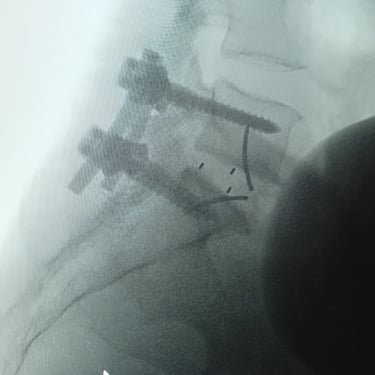

La cirugía ALIF (Anterior Lumbar Interbody Fusion), o Fusión Lumbar Intercorporal Anterior, es una técnica quirúrgica utilizada para tratar patologías de la columna lumbar como la degeneración discal, la inestabilidad vertebral o las hernias lumbares recurrentes. Mediante un abordaje anterior, se extrae el disco dañado y se coloca un injerto o caja intersomática que permite lograr la fusión estable entre las vértebras. Este procedimiento favorece una mejor restauración del espacio discal, alineación lumbar y preservación muscular. La cirugía ALIF es realizada por un equipo especializado en neurocirugía de columna, garantizando precisión y resultados funcionales óptimos.